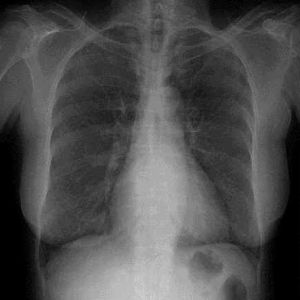

沙眼衣原體肺炎 1975年有人開始報告新生兒衣原體肺炎,繼發於包涵體膿性卡他之後。本病多由受感染的母親傳染可眼部感染經鼻淚管傳入呼吸道症狀多在出生後2~12周出現,起病緩慢,可先有上呼吸道感染表現多不發熱或偶有低熱,然後出現咳嗽和氣促,吸氣時常有細濕囉音或捻發音少有呼氣性喘鳴。胸片顯示雙側廣泛間質和肺泡浸潤,過度充氣征比較常見偶見大葉實變。周圍血白細胞計數一般正常,嗜酸性粒細胞增多從鼻咽拭子一定要刮取到上皮細胞。也可用直接螢光抗體試驗(DFA)、酶免疫試驗(EIA)檢測鼻咽標本沙眼衣原體抗原血清學檢查特異性抗體診斷標準為雙分血清抗體滴度4倍以上升高,或IgM>1:32,IgG>1:512也可套用PCR技術直接檢測衣原體DNA。

衣原體肺炎肺炎衣原體肺炎 本症臨床表現無特異性,與支原體肺炎楥相似。起病緩病程長,一般症狀輕,常伴咽喉炎及鼻竇炎為其特點。上呼吸道感染症狀消退後,出現乾濕囉音等支氣管炎肺炎表現。咳嗽症狀可持續3周以上。白細胞計數正常胸片無特異性,多為單側下葉浸潤,表現為節段性肺炎嚴重者呈廣泛雙側肺炎。病原學檢查與沙眼衣原體肺炎一樣,從氣管或鼻咽吸取物做細胞培養肺炎衣原體陽性。或用螢光結合的肺炎衣原體特異性單克隆抗體來鑑定細胞培養中的肺炎衣原體。PCR檢測肺炎衣原體DNA較培養更敏感但用咽拭子標本檢測似不夠理想,不如血清學檢測肺炎衣原體特異性抗體。微量免疫螢光(MIF)試驗檢測肺炎衣原體仍最敏感特異性IgM抗體≥1:16或IgM抗體≥1:512或抗體滴度4倍以上增高,有診斷價值。

輕症可無明顯症狀青少年常有聲音嘶啞、乾咳、有時發熱咽痛等咽炎、喉炎、鼻竇炎、中耳炎和支氣管炎等症狀,且可持續數周之久,發生肺炎通常為輕型與肺炎衣原體感染的臨床表現極為相似,並可能伴隨肺外表現如紅斑結節、甲狀腺炎腦炎和格林-巴利綜合徵。成年人肺炎多較嚴重,特別是老年人往往必須住院和呼吸支持治療有作者經血清學調查發現肺炎衣原體感染與冠心病之間有關聯,但尚須進一步確定。另外肺炎衣原體感染髮生哮喘的機制亦在研討之中。肺炎衣原體肺炎的肺部X線檢查常顯示肺亞段少量片狀浸潤灶廣泛實變僅見於病情嚴重者中。大部分患者血白細胞在正常範圍。

衣原體肺炎鸚鵡熱衣原體肺炎:胸部X線檢查,從肺門向周邊,特別向下肺野可見毛玻璃樣陰影中間有點狀影周圍血白細胞數正常,血沉在患病早期稍增快。肺泡滲出液的吞噬細胞內可查見衣原體包涵體輕症患兒3~7d發熱漸退。中症8~~14d,重症20~25d退熱病後免疫力減弱,可復發,有報導復發率達21%再感染率10%左右。

肺炎衣原體肺炎:白細胞計數正常,胸片無特異性,多為單側下葉浸潤表現為節段性肺炎,嚴重者呈廣泛雙側肺炎。病原學檢查與沙眼衣原體肺炎一樣從氣管或鼻咽吸取物做細胞培養,肺炎衣原體陽性。或用螢光結合的肺炎衣原體特異性單克隆抗體來鑑定細胞培養中的肺炎衣原體PCR檢測肺炎衣原體DNA較培養更敏感,但用咽拭子標本檢測似不夠理想,不如血清學檢測肺炎衣原體特異性抗體微量免疫螢光(MIF)試驗檢測肺炎衣原體仍最敏感。特異性IgM抗體≥1:16或IgM抗體≥1:512或抗體滴度4倍以上增高,有診斷價值。